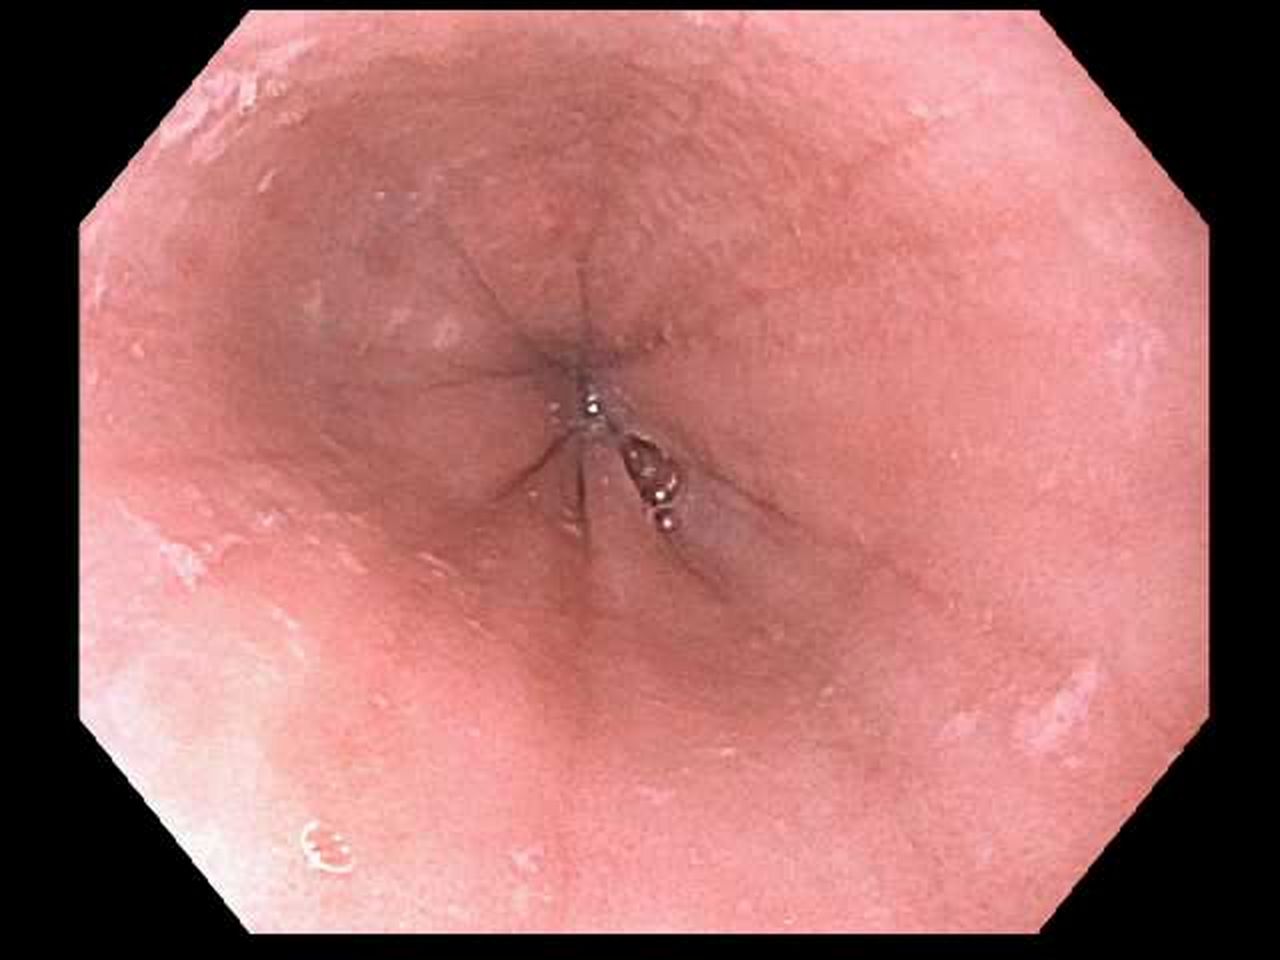

- Food impaction (Figure 1)

Figure 1. Food impaction in a patient with EoE.

Figure 1. Food impaction in a patient with EoE.

From Adamiak T, Plati KF. Pediatric esophageal disorders: diagnosis and treatment of reflux and eosinophilic esophagitis. Pediatr Rev. 2018;39(3):392-402.